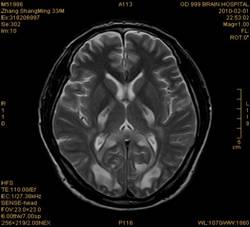

案例2 患者,女,30岁,二氯乙烷中毒性脑病的头颅MR。表现为双侧大脑半球皮层下白质、双侧外囊、双侧苍白球及双侧小脑齿状核内广泛片状、斑片状长T1长T2异常信号影,FLAIR序列呈高信号,增强后病变未见明显强化。

给予抗炎、脱水、疏通血管及营养神经等药物治疗。经过40天的对症治疗,痊愈出院。